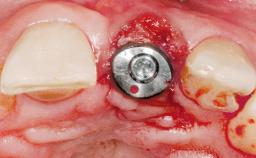

Immediate Flapless Placement of an Implant in a Maxillary Right Lateral Incisor Site

This 43-year-old male patient, a non-smoker, came to our practice because of a fracture of tooth 12 caused by a bicycle accident. Due to the combined para- and infrabony crown and root fracture, tooth extraction, and subsequent implant placement were suggested to the patient as the therapy of choice. The patient had high esthetic expectations with regard to the treatment outcome and asked for an immediate fixed provisional restoration. His individual esthetic risk profile summed up to a medium esthetic risk.

| Placement Protocol | Immediate implant placement |

| Socket Morphology | Single-root socket |

| Socket Integrity | Sufficient, with intact bone walls |